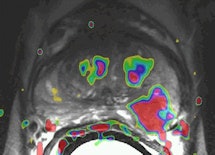

A 48-year-old sexually active male with PSA 9; TRUS biopsy Gleason 4+3 PC at right PZ; stage T1c. Nerve-sparing prostatectomy was performed showing submillimeter ECE and negative resection margins. Postsurgery patient was potent and continent. Left: Axial T2-weighted MR image shows low signal tumor in right PZ (white area) with obliteration of the white fat at the rectoprostatic angle (arrows), indicating minimal ECE = PI-RADS 5. The NVB is indicated by red, blue, and yellow. Right: Nerve-sparing prostatectomy showed Gleason 4+3 PC with submillimeter ECE (T; blue area) at right PZ. Resection margins were negative. Patient was potent after surgery.

A 48-year-old sexually active male with PSA 9; TRUS biopsy Gleason 4+3 PC at right PZ; stage T1c. Nerve-sparing prostatectomy was performed showing submillimeter ECE and negative resection margins. Postsurgery patient was potent and continent. Left: Axial T2-weighted MR image shows low signal tumor in right PZ (white area) with obliteration of the white fat at the rectoprostatic angle (arrows), indicating minimal ECE = PI-RADS 5. The NVB is indicated by red, blue, and yellow. Right: Nerve-sparing prostatectomy showed Gleason 4+3 PC with submillimeter ECE (T; blue area) at right PZ. Resection margins were negative. Patient was potent after surgery.One in six men in their lifetime will be clinically diagnosed with prostate cancer, and this accounts for 350,000 cases, annually or 25% of all new male malignancies diagnosed in Europe, the authors noted. Currently, digital rectal examination, serum prostate specific antigen (PSA) -- a nonspecific blood test -- and transrectal ultrasound-guided biopsy -- where the target is mostly invisible -- are used as diagnostic tools.